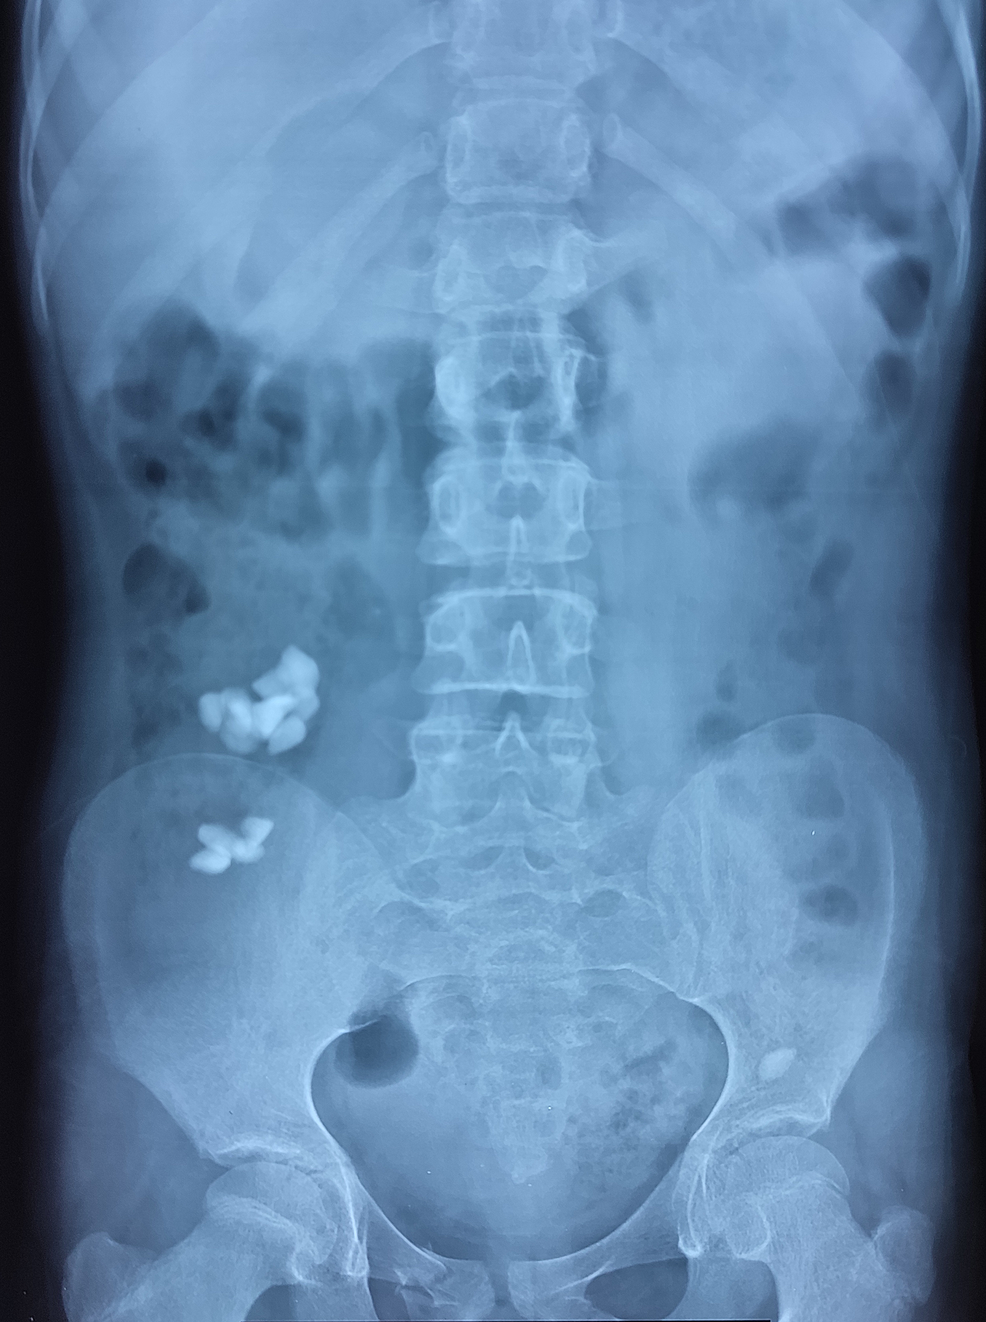

We present this interesting case of a 14-year-old female child with mental and developmental delay, who was incidentally diagnosed with massive colonic bezoar. The patient was brought to the emergency department of Hayatabad Medical Complex after a road traffic accident (pedestrian vs. vehicle) in September 2021. She was clinically stable during the primary and secondary surveys. She was complaining of mild bruises and pain in the right upper and lower limbs. To rule out any abdominal trauma, an abdominal X-ray was done, which revealed multiple irregular radiopaque shadows with the typical “corn on the cob” appearance extending from the cecum to the rectum. Figure 1 shows the initial plain abdominal X-ray.

Her blood investigations (Table 1) suggested microcytic anemia. Her condition improved significantly in a few days; hence, she was discharged home on laxatives, multivitamins, and iron supplements on the fourth day of admission, with a daily follow-up plan with serial X-rays for the next few days. On her one-week follow-up visit to the clinic, she was more active and smiling. There was a great deal of improvement noticed in her clinical status. The follow-up X-ray of the abdomen (Figure 3) revealed partial clearance of the lithobezoar. Laxatives were continued to ensure complete evacuation. She was referred to pediatric psychiatry and genetics for further evaluation. On a two-month follow-up visit, blood investigations showed improvement in the hemoglobin and iron levels and with that, the pica behavior was resolved.